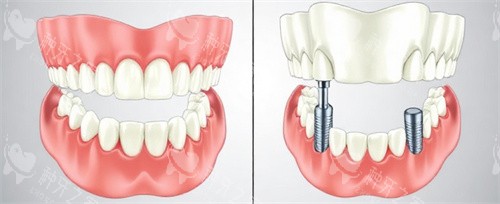

All-on-4全口修复

针对全口无牙患者,通过四颗种植体支撑整排牙桥,减少骨增量手术需求,缩短改善周期。

该技术尤其适合牙槽骨条件较差的老年群体,术后咀嚼功能改善显著。